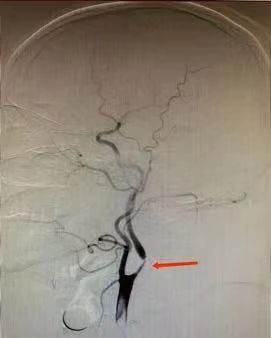

2023-05-16【医疗技术】神内卒中团队开通基底动脉1例

4月26日,10:47分:59岁男性王某,以“意识障碍40分钟”入我院,专科查体可见患者呈昏睡状态,反应迟钝,吐字不清,双眼向右凝视,四肢肌力5-级,NIHSS评分7分。 卒中... -